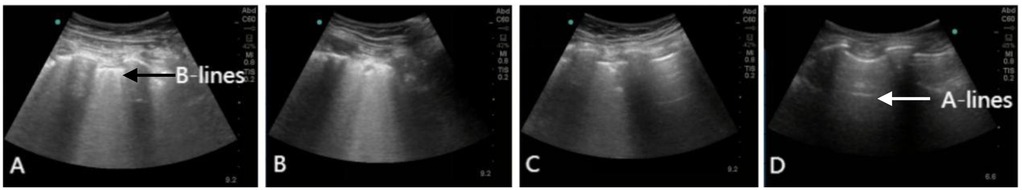

During his ICU stay, serial assessments—including CXR (Figures 1A–D), lung ultrasounds (Figures 2A–D), computed tomography (CT; Figures 3B,C), and blood gas analyses—were obtained to monitor his condition. The chest CT revealed significant exudation in the right dorsal segment. Based on this finding, prone positioning ventilation (PPV) was initiated as an adjunct to the ongoing VV-ECMO therapy to treat the RPE (Figure 3D). By postoperative day 10, the patient's CXR demonstrated marked improvement and lung auscultation findings were unremarkable, enabling the discontinuation of VV-ECMO. The patient was successfully extubated on postoperative day 12 and was subsequently discharged on postoperative day 30 without sequelae. Transthoracic echocardiography prior to discharge demonstrated normal function of the prosthetic valve. Informed consent was obtained from the patient for the publication of his clinical details and images.

Figure 2. Lung ultrasound showing the resolution of RPE. (A) Lung ultrasound on day 1 demonstrating diffuse B-lines in the right lower lung. (B–D) Serial lung ultrasounds performed on day 3, 10, and 30 show progressive improvement. Real-time lung ultrasound identified A-lines (white arrow) and B-lines (black arrow).

Although chest x-ray is convenient and provides a preliminary assessment of postoperative cardiopulmonary status, its accuracy in identifying imaging findings and underlying pathology is limited due to its anteroposterior projection and the constraints of the ICU environment. Lung ultrasound can serve as a powerful alternative to chest x-ray; compared to CT or x-ray, it allows more accurate classification of lung morphology. The anterior chest wall region is most accessible and useful for lung morphological classification (9). An increased number of B-lines on ultrasound is associated with elevated serum N-terminal pro-brain natriuretic peptide levels and an increased incidence of major adverse cardiovascular events (10). Due to its non-invasiveness, bedside availability, and widespread accessibility in various healthcare settings, lung ultrasound has an irreplaceable value in the diagnosis and management of RPE (11). It is also crucial for disease diagnosis, monitoring of disease progression, and evaluation of treatment efficacy. Bedside lung ultrasound facilitates rapid early recognition and management of RPE; real-time monitoring of cardiopulmonary function and early clinical intervention are also vital, enabling timely diagnosis and treatment.